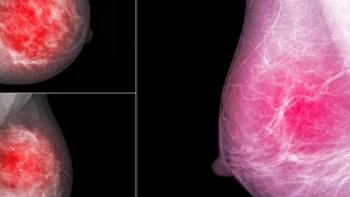

Consistent adherence to the five most recent mammography screenings prior to a breast cancer diagnosis reduced breast cancer death risk by 72 percent in comparison to women who did not have the mammography screening, according to new research findings presented at the annual Radiological Society of North America (RSNA) conference.

In a recent video interview, Susan Holley, MD discussed key findings from a large retrospective longitudinal study, presented at the recent Radiological Society of North America (RSNA) conference, which found that an emerging artificial intelligence (AI) model was over 24 percent more consistent than radiologist assessment of breast density.

An emerging artificial intelligence algorithm, developed to estimate volumetric breast density from 3D-reconstructed digital breast tomosynthesis images, could potentially facilitate individual risk assessments for breast cancer.